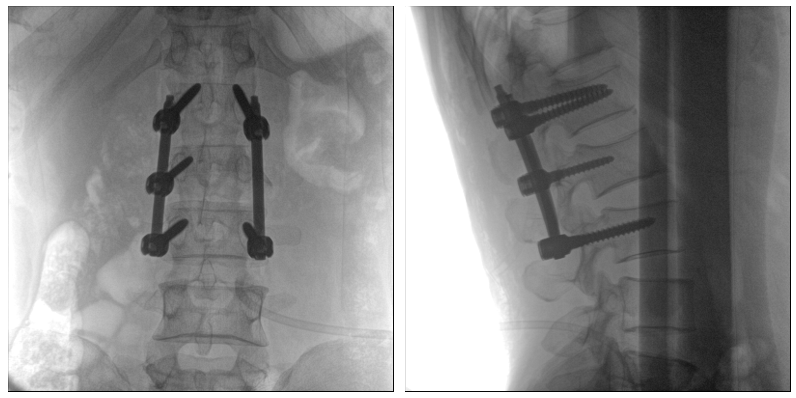

术中二维影像

从图中可以看到二维影像能够提供目标区域在某一个平面的重叠影像,虽然因为人体不同组织的密度差异,使得图像具有较为丰富的信息量,但组织间的相互重叠还是会出现,诸如空间位置等众多信息在影像中遗失或不可辨认的情况,影响了医生对信息的收集与应用。